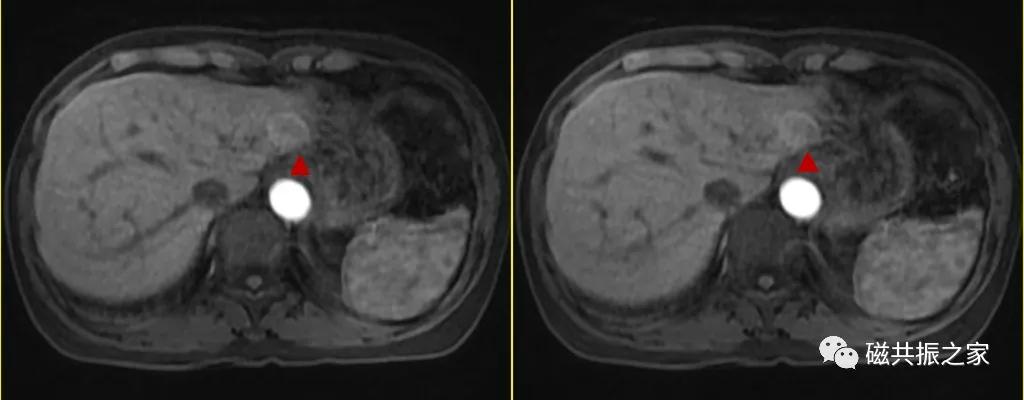

【为了节省扫描时间,肝脏可以这么扫】

注:特异性期应根据不同的对比剂调整扫描时间,可参考说明书。

优化后的流程不但节省了扫描时间,延迟时间也延迟到位了。

你也不必担心注射对比剂后T2WI和DWI对病灶的显示及图像质量的影响,研究表明不管是在对比剂注射前或后扫描T2WI、DWI,几乎不会对MRI图像造成影响。